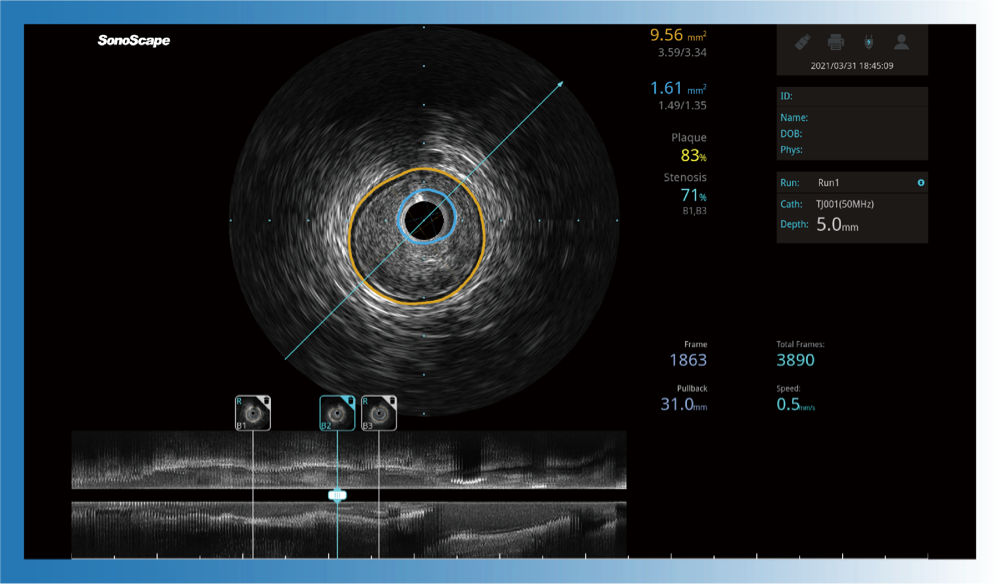

对比传统IVUS导管成像,DB中国旗舰官方网站宽频IVUS图像的近场支架梁显影更细腻,远场中膜外血管仍清晰可辨,兼顾远中近,兼顾分辨力与穿透深度

一键智能描迹,自动测量斑块负荷、面积狭窄率等指标,准确率高于90%